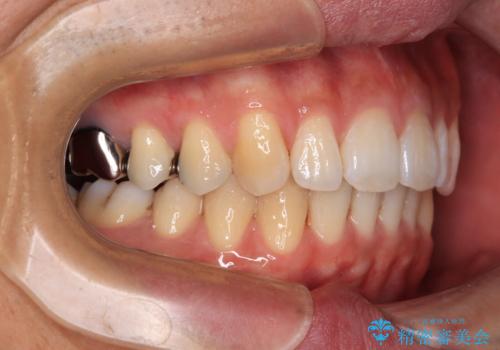

深い咬み合わせと前歯の隙間 ハーフリンガルによる矯正治療

矯正治療中に結婚式があったそうですが、隙間も改善しており、一部装置を外すことなく挙式できたとのことでした。